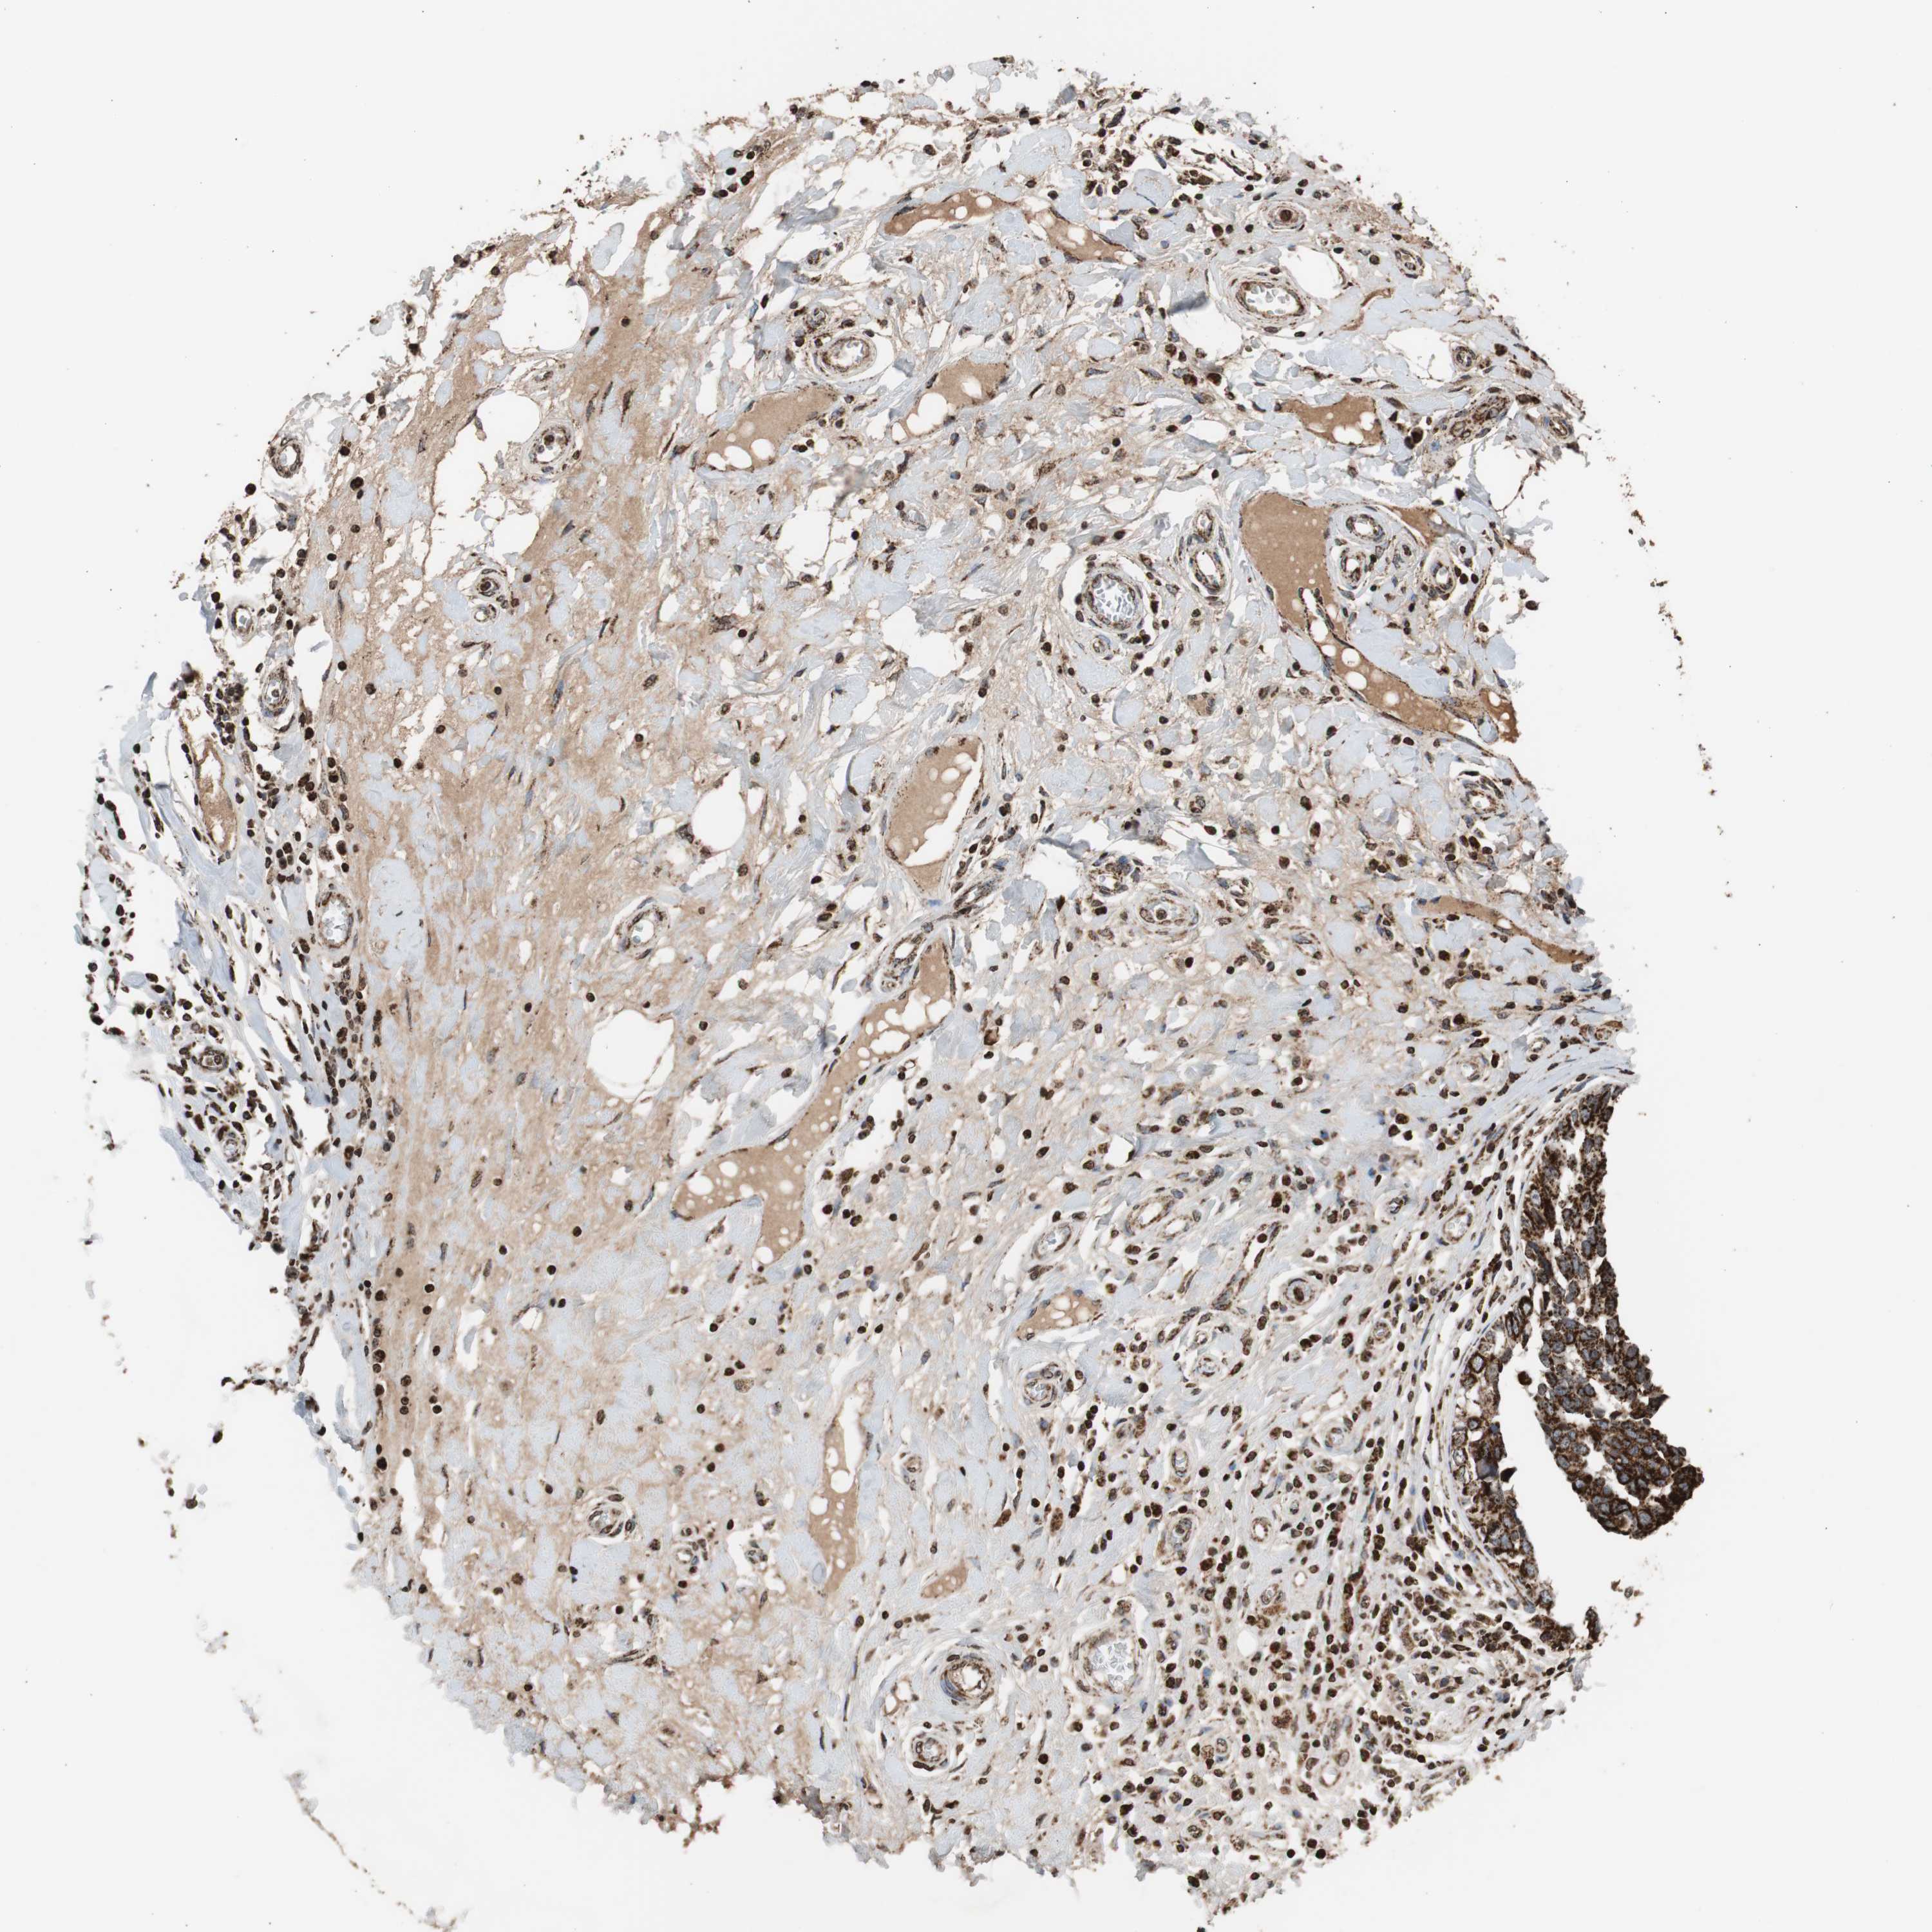

CANCER BREAST CANCER Show tissue menu

BRCA TCGA BRCA VALIDATION PROTEIN EXPRESSION